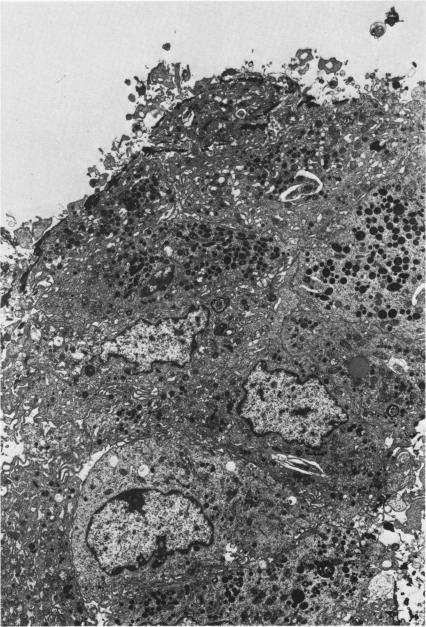

Desquamative interstitial pneumonia. An electron microscopic study.

Am J Pathol. 1970 Sep;60(3):347-70.